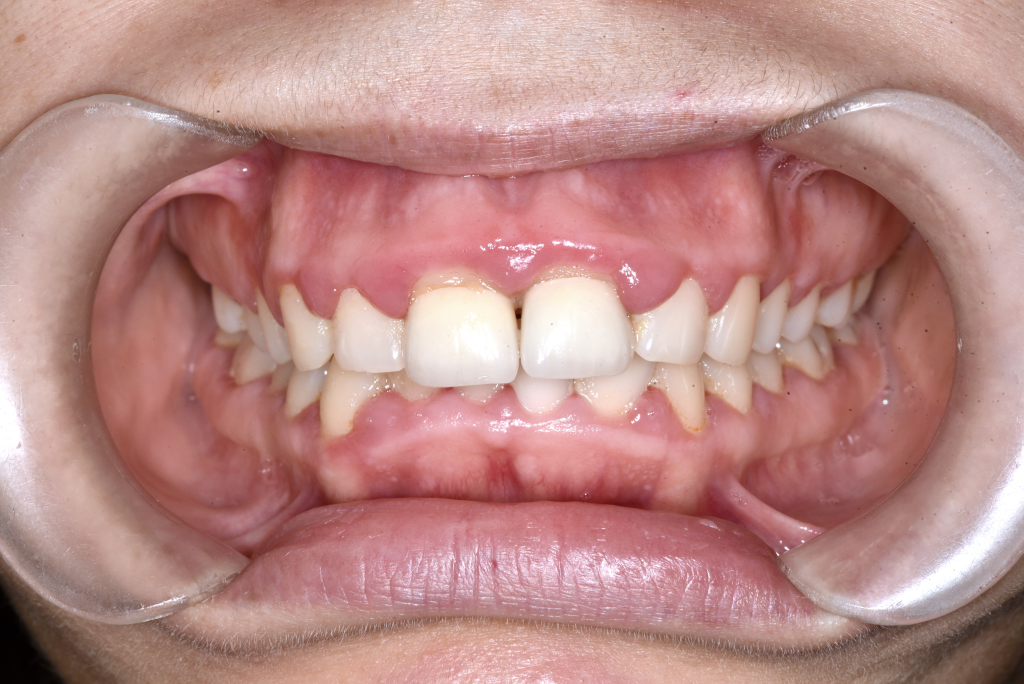

Előtte fogsor - Állcsonti aszimmetria kezelése

Ebben az esetben az arc és a harapás nem egy középvonal mentén működött.

Az alsó állkapocs oldalirányú eltérése instabil harapást és aszimmetrikus mosolyt okozott.

A probléma nem fogállási, hanem állcsonti eredetű volt.

A kezelést fogszabályozással készítettük elő, majd

mindkét állkapocs műtéti áthelyezésével szimmetrizáltuk a harapást és az arc középvonalát.

Eredmény: kiegyensúlyozott harapás, rendezett arcarányok, természetes mosoly.